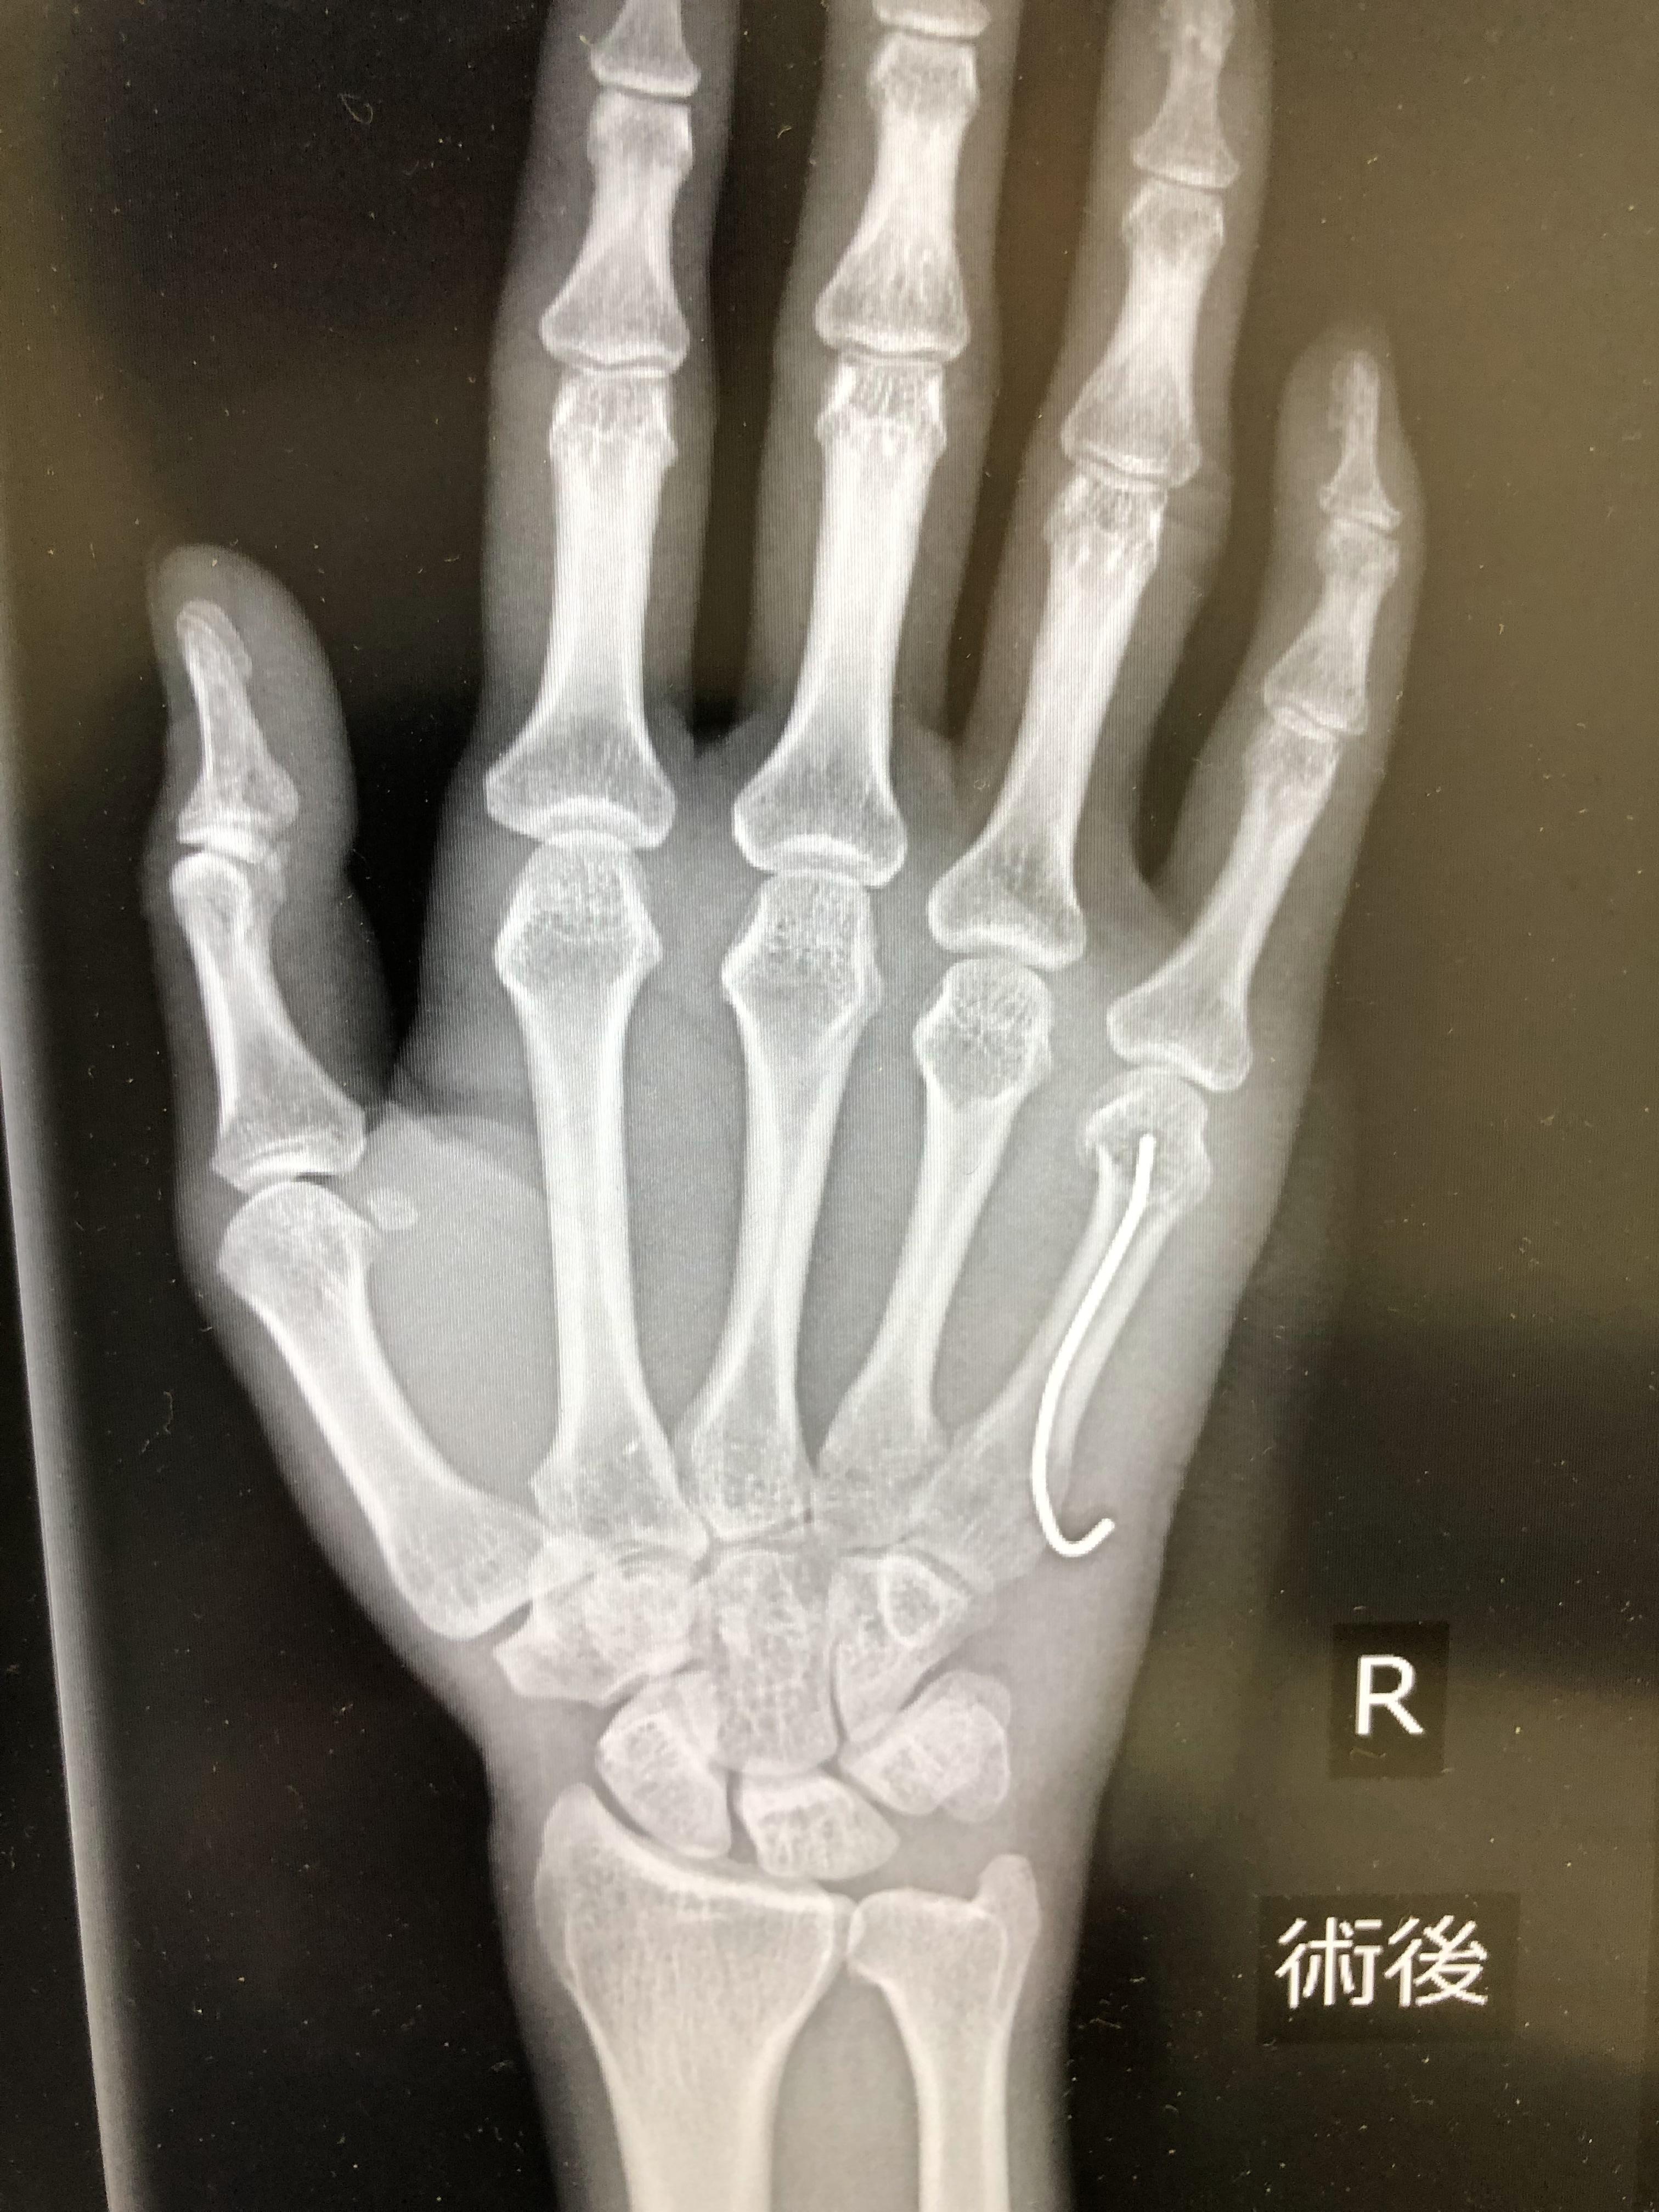

어찌저찌하다가 새끼손가락 뼈가 휘여서 철심을 박았습니다. ㅠ.ㅠ

보이시나요? 새끼손가락 안에 들어간 저 철심 ㅠ.ㅠ

하..... 어쩌다가 이리 됐는지....